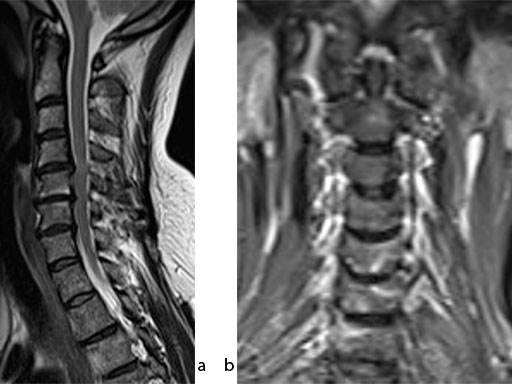

A 51-year-old woman was affected by cervical radiculo-myelopathy due to spinal and neuroforaminal stenosis. The preoperative CT scans are shown at Fig 4 and MRI at Fig 5.